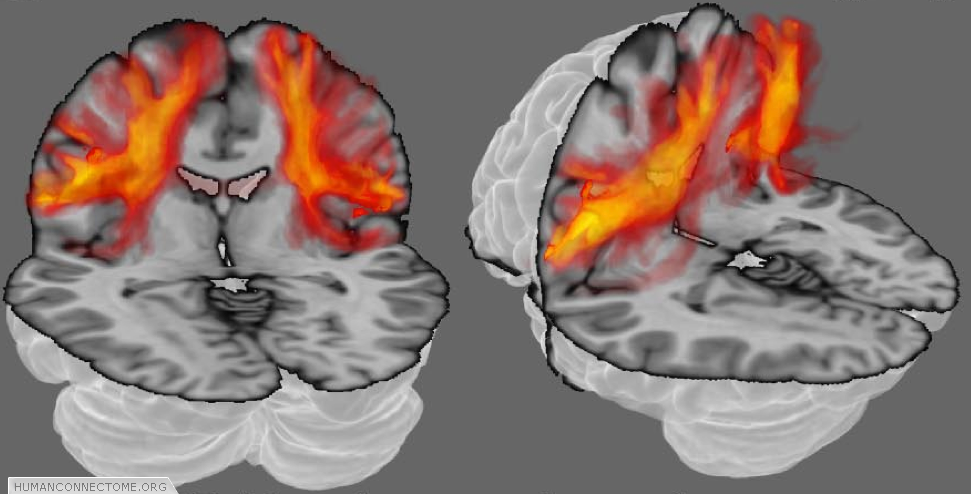

Because our measurements come from voxels that are much larger than axons, each point in the brain does not have just one connection, but many. Furthermore, because our measurements contain errors, and our models can never be perfectly accurate, even if there were only one connection we would always be uncertain as to its exact pathway. Deterministic tractography, depicted in figure 1, can never account either for uncertainty or for distributed connectivity. Because of this, the HCP is working with probabilistic tractography. At every voxel, we estimate “most likely” fiber orientations (as in figures 1 and 2), but we also estimate a distribution representing how likely each other orientation is to lie along a fiber. Then, when we trace the connections, we trace thousands of times, each time using slightly different orientations (according to their likelihood). The set of all these different paths are then collectively a measure of the connection likelihood or probability  (Figure 3).  The HCP is investing significant effort in optimizing such probabilistic approaches and adapting them with new models to provide the most robust estimates of distributed connectivity for the Connectome.

Figure 3: Probabilistic tractography. The orange clouds show color coded connectivity distributions determined by probabilistic tractography. Each voxel (point in space) is assigned a color from a hot-iron scale where black (no color in this case) means that there is zero connection probability, red-hot indicates intermediate probability and white-hot indicates a high connection probability.